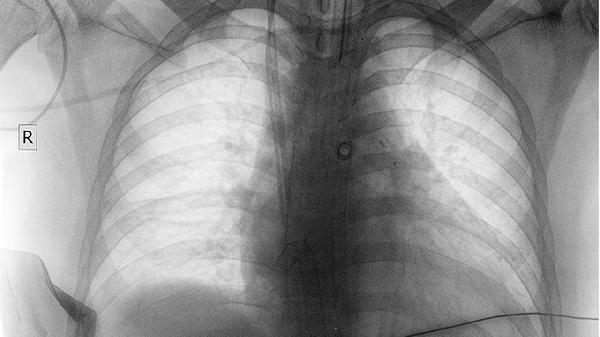

浸润导管癌2级是早期么

浸润导管癌2级属于早期乳腺癌的一种,通常通过手术、放疗和内分泌治疗进行综合治疗。浸润导管癌2级表示癌细胞分化程度中等,侵袭性相对较低,但需及时干预防止进展。

治疗方法包括手术切除肿瘤、放疗杀灭残留癌细胞、内分泌治疗抑制激素依赖性癌细胞的生长。手术方式可选择保乳手术或全乳切除术,放疗通常在手术后进行以减少复发风险,内分泌治疗适用于激素受体阳性的患者,常用药物有他莫昔芬、来曲唑等。

浸润导管癌2级虽然属于早期,但仍需重视综合治疗和定期随访,通过多学科协作和个性化治疗方案,患者可以获得良好的预后和生活质量。